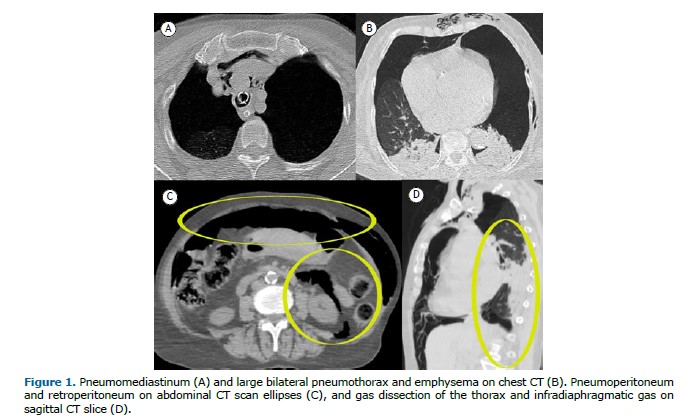

An 80-year-old woman with systemic arterial hypertension was admitted to the emergency department after a transient loss of consciousness. On arrival, she presented with hypoxemia and decreased sensorium, requiring orotracheal intubation. Chest computed tomography (CT) revealed a large bilateral pneumothorax, pneumoperitoneum, and retroperitoneal air (Figure 1). A chest tube was placed. An initial suspicion of hollow viscus perforation was ruled out after exploratory laparotomy showed no visceral injury. The combination of imaging findings and clinical context strongly suggested barotrauma secondary to excessive positive-pressure ventilation. This likely resulted in alveolar rupture due to elevated intrathoracic pressure, with air dissecting along bronchovascular sheaths—a phenomenon known as the Macklin effect. From the lungs, air extended into the mediastinum and, in rare cases, progressed as gas dissection through mediastinal vessels into the retroperitoneal space and peritoneal cavity, leading to pneumoperitoneum without visceral perforation. The patient subsequently developed an ischemic stroke and died following clinical deterioration.

Pulmonary barotrauma is uncommon but potentially life-threatening, resulting from sudden increases in intrathoracic pressure. Common complications, such as hypoxemia and subcutaneous emphysema, are typically managed conservatively. However, gas dissection into the retroperitoneum and peritoneum, though rare, represents a serious and diagnostically challenging condition. Early recognition through CT is essential for timely and appropriate management.(1–2)